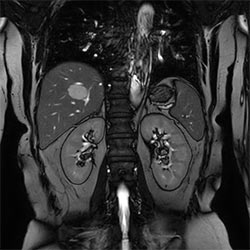

Pelvis